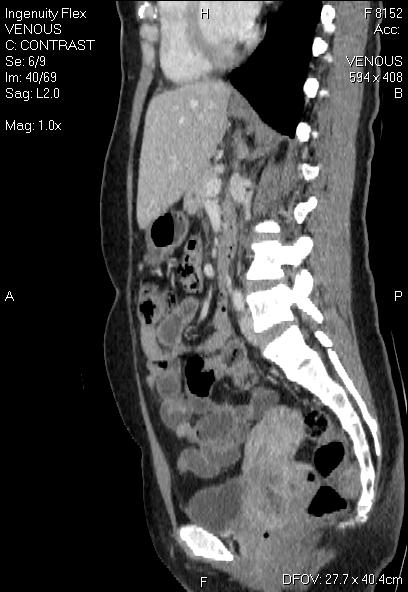

CT-ung thư vòm-di căn gan phổi